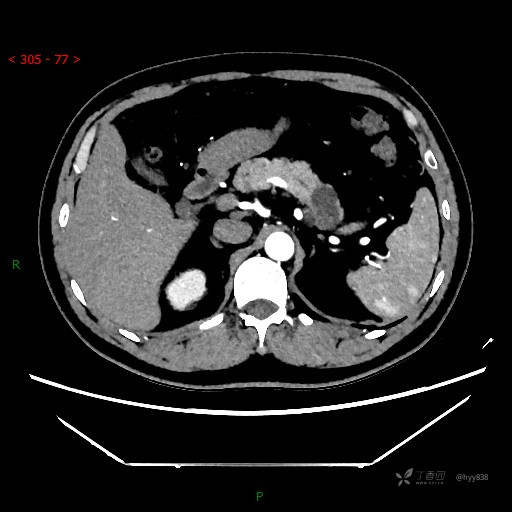

腹部CT平扫